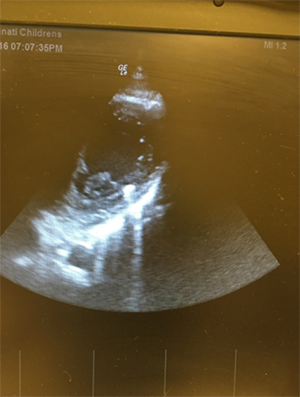

An electrocardiogram showed normal sinus rhythm. Cardiothoracic surgery was immediately consulted. Given the patient’s hemodynamic stability, he was taken for a CTA of the chest (Figures 3–5) to delineate the injury and plan surgical intervention. Imaging showed injury to the medial right chest with pulmonary contusion and laceration extending to the anterior aspect of the right hilum. The metallic pellet was identified within the cavity of the left ventricle. There was a small right hemothorax and a tiny pneumothorax.

Figure 3. Coronal view demonstrating bullet track and foreign body inside the left ventricle.

Figure 4. Axial view depicting bullet inside the left ventricle.

Figure 5. Axial view depicting bullet track near the pulmonary veins.